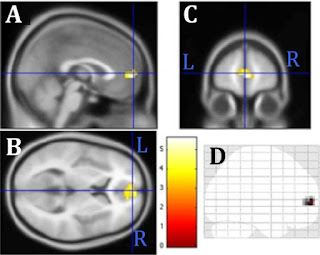

Activity of the medial prefrontal cortex after psycho-spiritual healing (Baldwin et al., 2016).

Everything we do and feel and experience changes the brain. Psychotherapy, juggling, taxi driving, poverty, reading, drugs, art, music, anger, love. If it didn't we'd be dead. Why should prayer be any different? The trick is to accurately determine the structural or physiological changes that are unique to a specific activity. And when assessing the effectiveness of clinical interventions, how the changes compare to an adequately matched control intervention. Plenty of high profile studies have failed to do that, including a recent one on emotionally focused therapy.1

2 These Bad Memory/Feeling blocks were also compared to Neutral Memory/Feeling blocks that evoked memories and feelings about a neutral topic (e.g., the weather). This is the pre/post contrast shown in the first figure of the post.